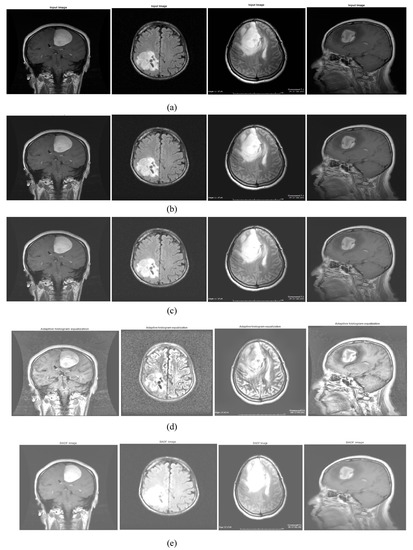

2.1. Image Acquisition

Available Datasets